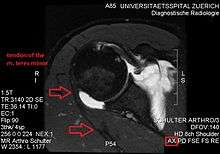

Atrophy of the teres minor muscle is often a consequence of a rotator cuff tear, but common isolated teres minor atrophies have also been found. A quadrangular space syndrome causes excessive and or chronically compression of the structures which pass through this anatomical tunnel. The axillary nerve and the posterior humeral circumflex artery pass through the space. People affected note shoulder pain and paresthesia down the arm first and foremost in abduction, extension, external rotation and overhead activity. Selective atrophy of the teres minor muscle has been seen and pulled together directly with compression of the corresponding axillary nerve branch or posterior humeral circunflex artery. Fibrous bands, cysts of the glenoid labrum, lipoma or dilated veins can occupy the quadrilateral space pathologically. Similar symptoms are common with anterior shoulder dislocation, humeral neck fracture, brachial plexus injury and thoracic outlet and inlet syndrome. It is important to include those pathologies for a complete as possible differential diagnosis.

Ultrasonography is a tool to detect a fatty degenerative atrophy of the teres minor and shows in affected muscles increased echogenicity and betimes a slight reduction in muscle bulk. MR imaging helps to consolidate the diagnosis of neurogenic muscle atrophy. Extracellular edema after traumatic events causing neural damage show an increased signal intensity on T2-weighted MRI sequences and normal intensity on T1-weighted sequences. Posterior humeral circunflex artery compression and reduced blood flow in stressful arm positions and or maneuvers can be diagnosed by a Doppler ultrasonography. The nerve should be detected adjacent to the vessel. In an elevated arm position the axillary neurovascular bundle can be seen at the posterior axillary fold just before it perforates the deltoideus, while the posterior course is well visible in the neutral position. For a detailed assessment of the artery, a MR angiography is required. The major task of an ultrasonographic examination is to rule out any space occupying mass. Additional electromyography is helpful to reveal any decelerated nerve conduction velocity, and thus denervation of the concerned muscle.[6]